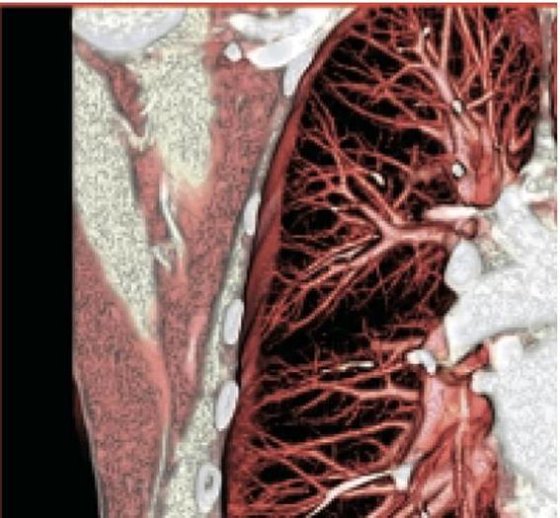

2004 GE LIGHTSPEED 16 SLICE CT SCANNER. Detector channels: 16 x 912. Scan Times:360 degrees, 0.5-0.9 and 1,2,3,4. Slice Thickness mm-0.625, 1.25, 2.5, 3.75, 5, 7.5, 10mm. Gantry Tilt: 30 degrees. X-Ray Tube: 6.3 mHu. X-Ray Generator: 53.2 kW, 10-440 mA’s. Spiral Scanning: yes, Max. scan time: 120 seconds, Max. scan volume: 170 cm. Reconstruction time: 0.1667 seconds. Computer CPU-Open architecture (LINUX). Maximun umber of images displayed at once: 16. Archival Storage: 2.3 GB MOD DICOM 3. CT Angiography: Standard (MiP), and DICOM 3.0 Interface-yes. OPTIONAL: CT Simulation and 3-D Package. This system is available soon. Subject to prior sale.

The used GE Lightspeed RT 16 CT machine is considered one of the world’s leading CT scanners for cancer care. The GE Lightspeed RT 16 CT scanner is a wide-bore system that is easy to operate and features predefined protocols that allow your to perform a wide variety of applications fast and efficiently while delivering exceptional comfort to your patients. This used CT scanner has the power to tackle 3D and 4D imaging as well as display different images simultaneously in real-time..

The refurbished Lightspeed RT 16 is known to be easy-to-use and its ability to display multiple 3D and 4D images simultaneously. The Lightspeed 16 radiotherapy CT is also popular because of its wide-bore opening of 80cm.